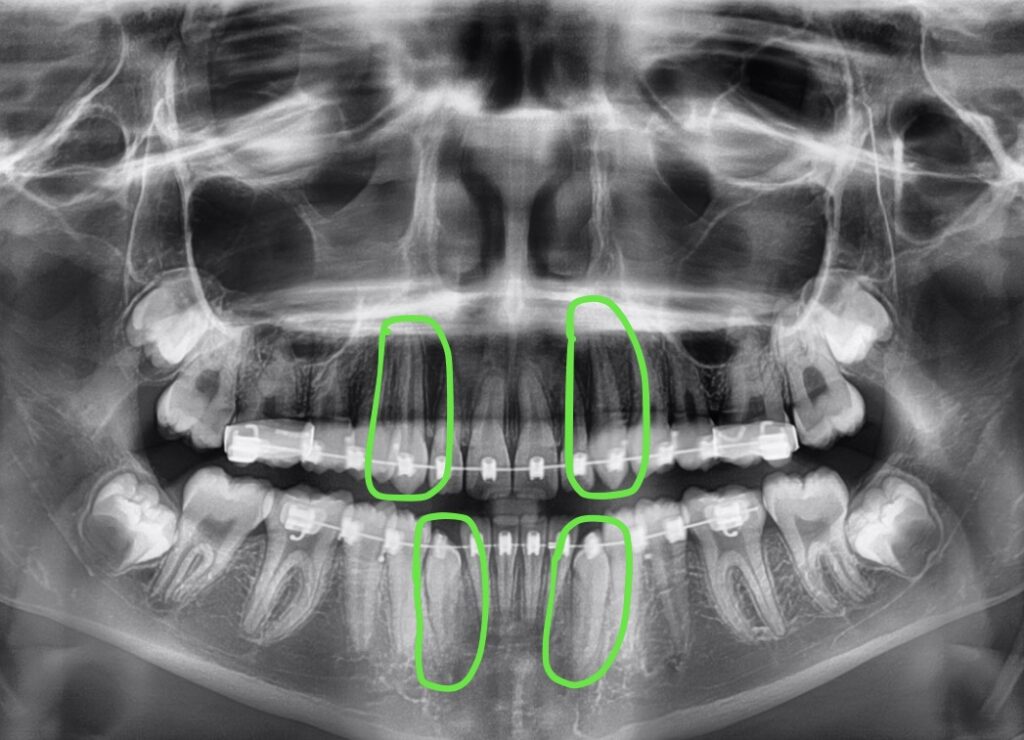

Results. Once the canine teeth have fully erupted, we place full braces on the teeth until they are straightened and in line with the rest of her teeth. The x-ray below shows the canine teeth, now in the corrected positions.

Finally, Lauren had all the braces removed. What a beautiful full smile and a happy patient! Lauren started treatment at age 11. Her treatment lasted two and a half years, allowing time for the canine teeth to move properly and slowly through her bone.